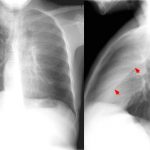

RIGHT UPPER LOBE ATELECTASIS

The archive below organizes different examples of a right upper lobe atelectasis. It will really be the anatomical location of the finding that will help diagnosis this SPECIFIC subtype of atelectasis. Click on the thumbnails below to view the archive.

RIGHT MIDDLE LOBE ATELECTASIS

The archive below organizes different examples of a left middle lobe atelectasis. It will really be the anatomical location of the finding that will help diagnosis this SPECIFIC subtype of atelectasis. Whats more, this type of atelectasis often obscures the right cardiac border. Click on the thumbnails below to view the archive.

RIGHT LOWER LOBE ATELECTASIS

The archive below organizes different examples of a right lower lobe atelectasis. It will really be the anatomical location of the finding that will help diagnosis this SPECIFIC subtype of atelectasis.Whats more, this type of atelectasis often obscures the border of the right diaphragm. Click on the thumbnails below to view the archive.

LEFT UPPER LOBE ATELECTASIS

The archive below organizes different examples of a left upper lobe atelectasis. It will really be the anatomical location of the finding that will help diagnosis this SPECIFIC subtype of atelectasis. Click on the thumbnails below to view the archive.

LEFT LOWER LOBE ATELECTASIS

The archive below organizes different examples of a left lower lobe atelectasis. It will really be the anatomical location of the finding that will help diagnosis this SPECIFIC subtype of atelectasis. Click on the thumbnails below to view the archive.